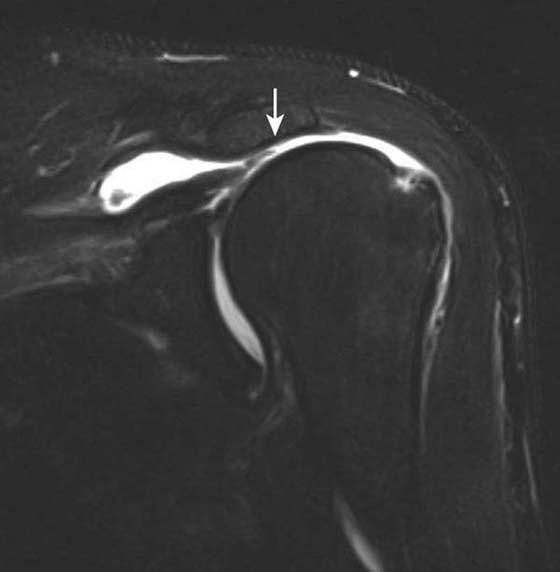

Instability

Radiography is useful in defining osseous alignment at the glenohumeral joint and may demonstrate a Hill–Sachs or bony Bankart’s lesion. CT also has utility in the assessment of osseous structures after subluxation/dislocation, particularly in evaluation of a subtle Bankart’s fracture with an equivocal MRI or intra-articular osseous fragments.21 CT is useful as a preoperative exam to assess fragment size and displacement. MR arthrography is the most sensitive test for evaluation of most of the causes, manifestations, and sequellae of glenohumeral instability.22-24 It allows for precise evaluation of the capsulolabral and ligamentous complex. Labral tears are diagnosed when intra-articular contrast material tracks into or underneath the labrum. Noncontrast MRI is also very sensitive, although use of a high-field scanner (≥0.7 T) is recommended. Labral tears most commonly associated with instability are anteroinferior or posterior (Fig. 14-9). Superior labral tears that track anterior to posterior (SLAP tears) are well seen with MR arthrography but are not usually associated with instability25,26 (Fig. 14-10). Tendon tears that can be associated with instability, including tears of the long head of the biceps tendon or subscapularis, are also well seen by MR arthrography and noncontrast MRI. Multidirectional instability typically shows no abnormality on imaging modalities, although capacious recesses may be observed.

images

Figure 14-10 Superior labral anterior to posterior (SLAP) lesion. Coronal fat-suppressed T1-weighted image of the shoulder after intra-articular gadolinium injection (direct MR arthrogram) demonstrates abnormal tracking of contrast material into the superior labrum (arrow) consistent with a SLAP tear.